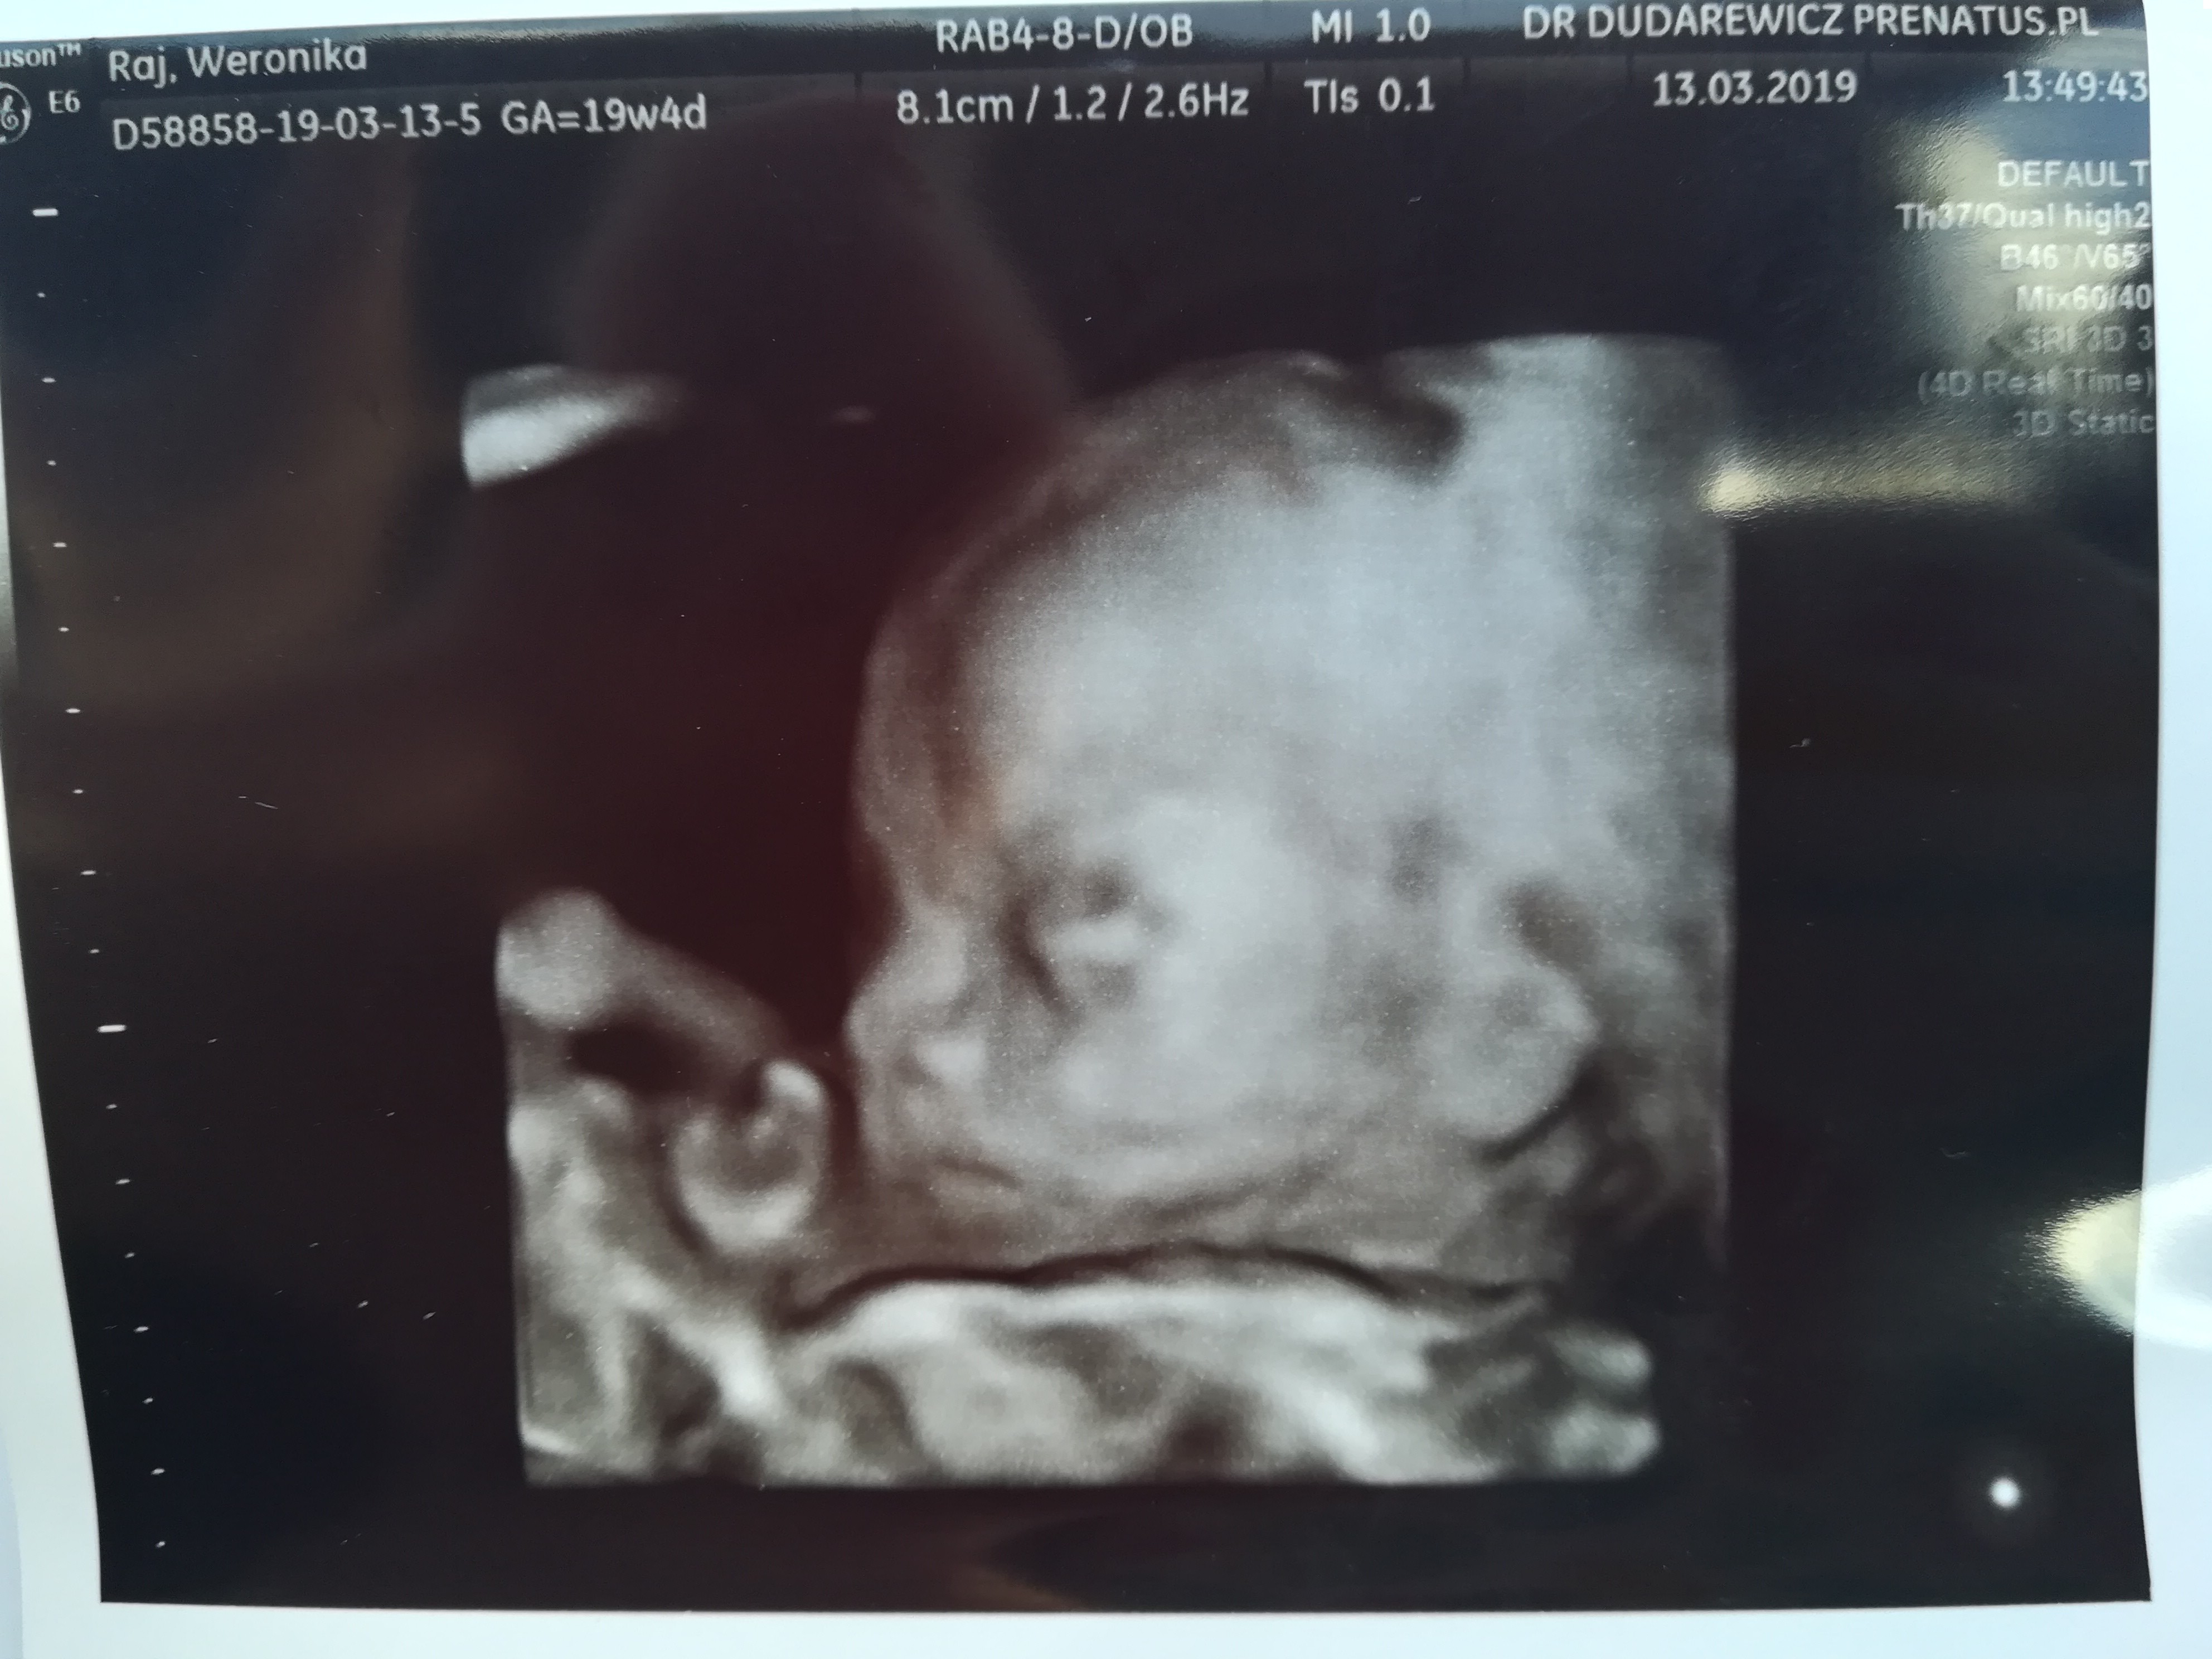

Dziewczyny, jestem już po połówkowym. Tak jak mówiłyście - wszystko w porządku. Serduszko zbadane, mózg, każdy narząd. Widać było nawet języczek :) dzidziuś waży 305 g i mierzy ponad 20 cm. Jedyne niepokojące okazało się badanie nerek i kanalików nerkowych, w których zalega mocz, w 30 tyg jest to do ponownego skontrolowania. Pan doktor zapytał czy chcemy z mężem poznać płeć - zgodnie stwierdziliśmy, że tak - no i okazało się, że nasze Marzenie się spełni - to CHŁOPCZYK!! :) pytałam 10

Razy czy na pewno, doktorek nie widział ani macicy, ani jajników, badał genitalia bardzo dokładnie, więc tym razem na pomyłkę już się nie nastawiam :) A córcia jak się ucieszyła, że będzie miała braciszka!